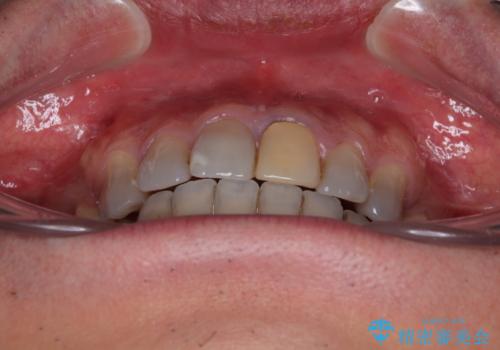

- 飛び出した前歯を気にして来院された患者様です。

口元を引っ込めるために上下左右の第一小臼歯4本を抜歯することとしました。

特徴的な歯の色が気になっているとのことで、今後セラミッククラウンによる審美歯科治療を検討されているとのことで、矯正治療の後戻りが落ち着いたタイミングで治療を進めていく予定です。